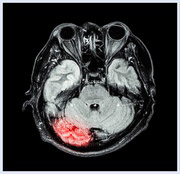

It is often said that 'a picture tells a thousand words'. While this is undoubtably true, it is also true that pictures can fool us into believing all sorts of things, simply because we tend to believe what we see.

Nowhere is this more true than in the world of brain scans. Pictures from fMRI scanning machines are popping up all over the place, with the implication being that they provide the proof for whatever it is that is being claimed. But how reliable is this evidence?